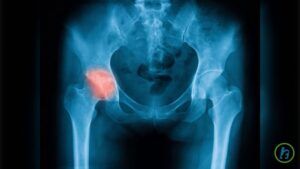

Coxartroza sau artroza şoldului este o boală cronică degenerativă care apare în urma distrugerii treptate a cartilajului dintre articulaţii, precum şi a inflamaţiei suprafeţelor articulare ale oaselor. În timp, boala duce la măcinarea cartilajului articular, provocând astfel dureri puternice și pierderea mobilității.

Cele mai multe cazuri de coxartroză apar după vârsta de 60 de ani, risc mai mare pentru a face boala având persoanele cu moștenire genetică în acest sens, persoanele supraponderale, precum și cele care au suferit traumatisme la nivelul articulației șoldului.